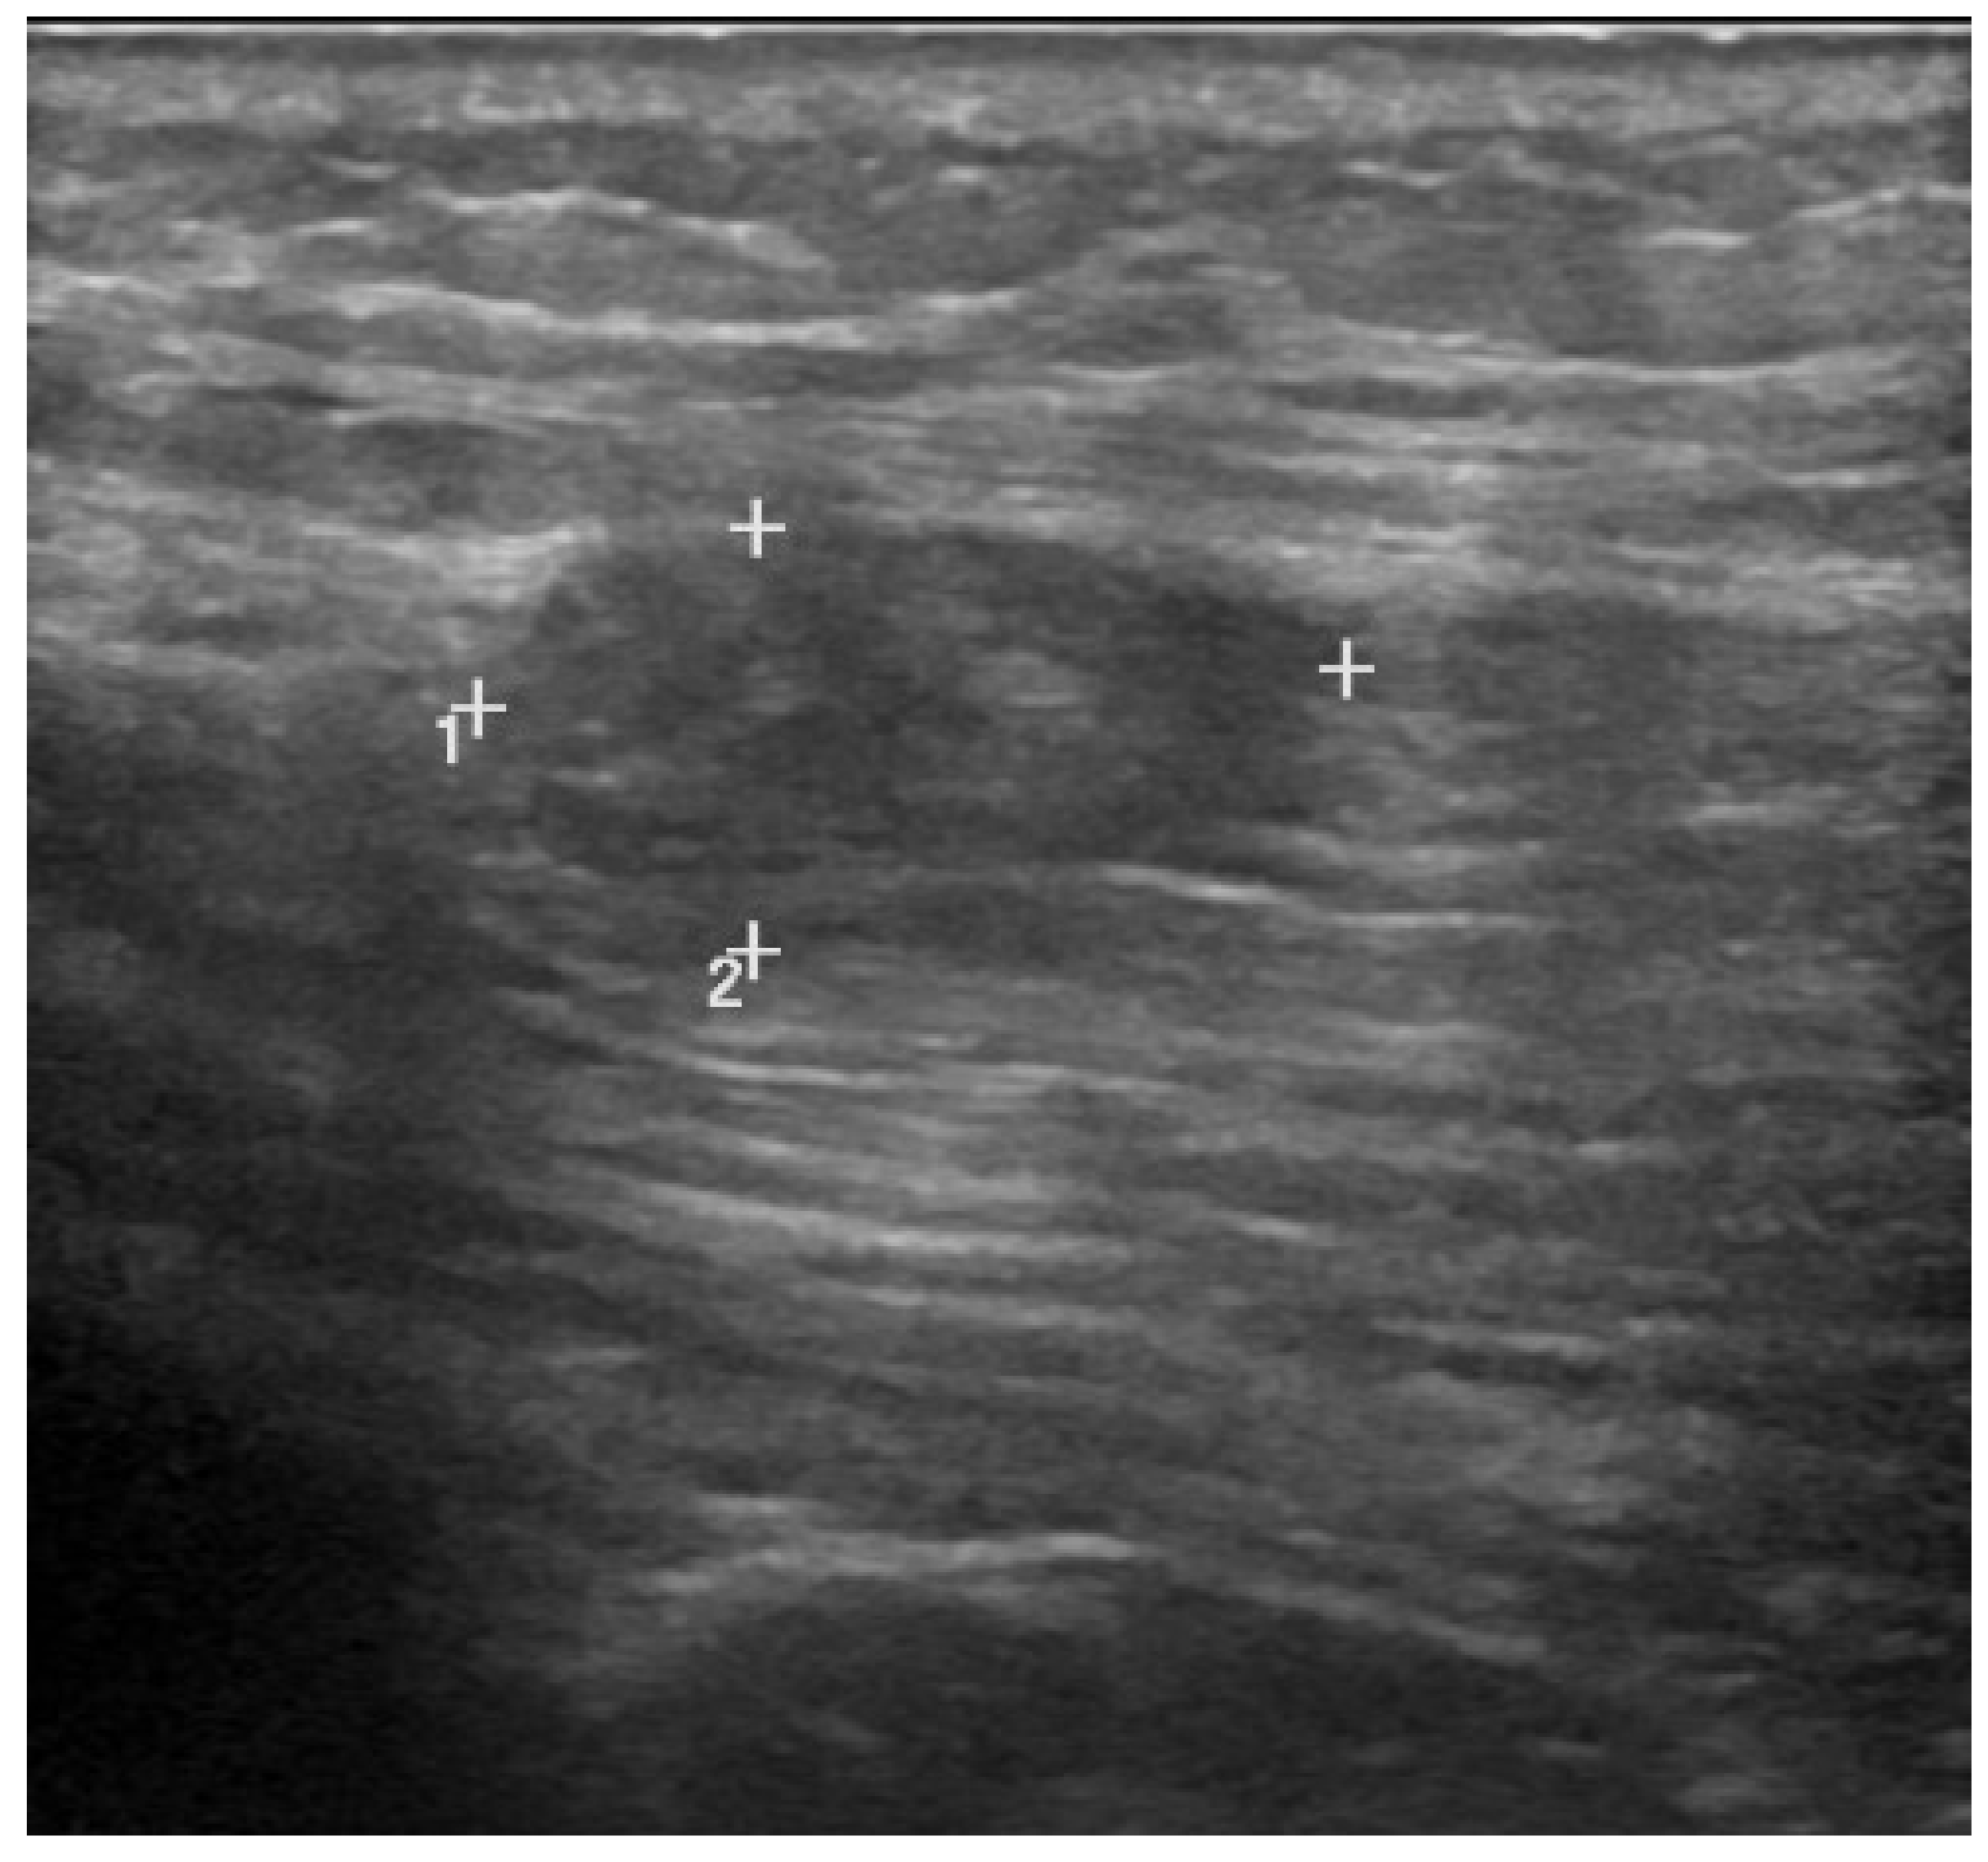

5. Ultrasound Findings of the Muscle Lesions

| Grade I | “<20% cross-sectional area.” | “Minimal elongations with less than 5% of muscle involved.” | “Normal, or focal/general areas of increased echogenicity +/− peri-fascial fluid.” | “Normal appearance; focal or general increased echogenicity with no architectural distortion.” |

| Grade II | “20–50% cross-sectional area.” | “5–50% muscle involvement, partial muscle rupture, demonstrable hypo or an echoic gap, with “bell clapper” sign.” | “Discontinuity of muscle fibers in echogenic perimyseal striae; hypervascularity around disrupted muscle fibers; intramuscular fluid collection; partial detachment of adjacent fascia or aponeurosis.” | “Discontinuous muscle fibers; disruption site is hypervascularized and altered in echogenicity; no perimyseal striation adjacent to the MTJ.” |

| Grade III | “>50% cross-sectional area.” | “Complete tear of muscle or fascia, with extravasation of collection away from injured part of muscle.” | “Complete myotendinous or osteotendinous avulsion; complete discontinuity of muscle fibers and associated hematoma; “bell clapper” sign.” | “Complete discontinuity of muscle fibers; hematoma and retraction of the muscle ends.” |